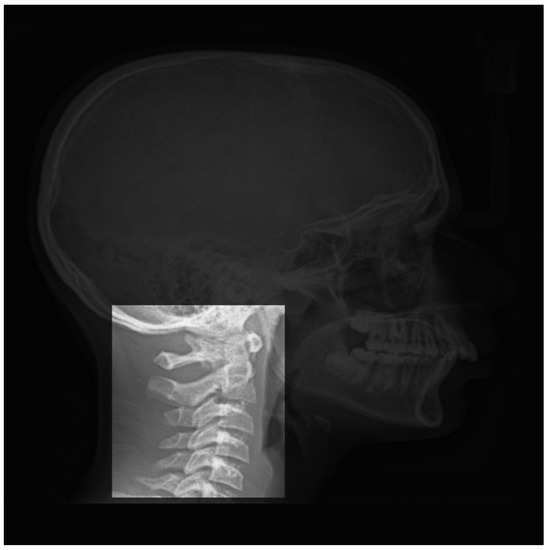

3.2. Vertebrae Maturation CVM:

- Cervical stage 1 (CS1) = 2 years before mandibular growth peak:Lower borders of C2 to C4 vertebrae are flat. C3 and C4 superior borders are tapered from posterior to anterior.

- Cervical stage 2 (CS2) = 1 year before mandibular growth peak:Lower border of C2 presents a concavity. Bodies of C3 and C4 are the same.

- Cervical stage 3 (CS3) = during the year of the mandibular growth peak:Lower borders of C2 and C3 present concavities. Vertebrae are growing so C3 and C4 may be either trapezoid or rectangular shape, as superior borders are less and less tapered.

- Cervical stage 4 (CS4) = 1 or 2 years after mandibular growth peak:Lower borders of C2, C3 and C4 present concavities. Both C3 and C4 bodies are rectangular with horizontal superior borders longer than higher.

- Cervical stage 5 (CS5) = 1 year after the end of mandibular growth peak:Still concavities of lower borders of C2, C3 and C4. At least one of C3 or C4 bodies are squared and spaces between bodies are reduced.

- Cervical stage 6 (CS6) = 2 years after the end of mandibular growth peak:The concavities of lower borders of C2 to C4 have deepened. C3 and C4 bodies are both square or rectangular vertical in shape (bodies higher than wide)